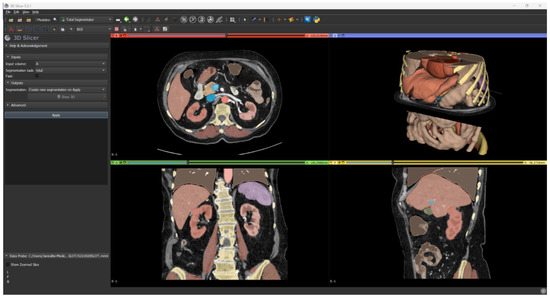

Renal parenchyma, aorta, and inferior vena cava were segmented using an automatic tool based on AI software. The TotalSegmentator tool [13] by 3D Slicer (https://www.slicer.org/, accessed on 7 June 2023) currently represents the gold standard in the artificial intelligence segmentation process.

It takes as input any CT scan series and it can segment in automatic the anatomical structures of interest, such as abdominal organs, muscles, bones, and large vessels (Figure 4).

Figure 4. Result of automatic segmentation.